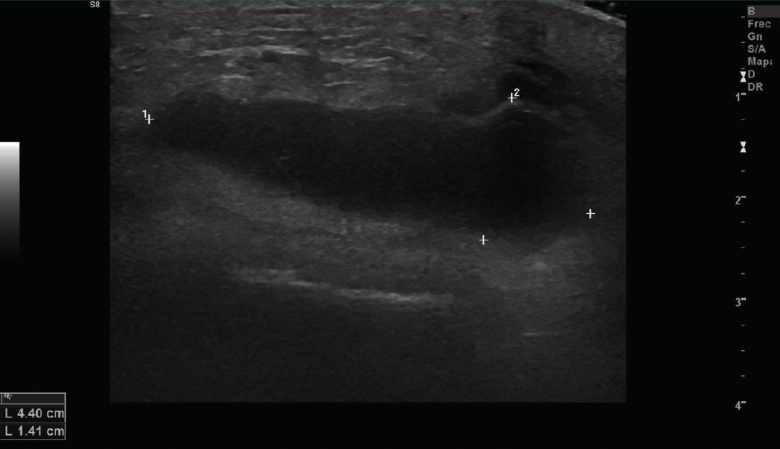

Figura 10. Corte sagital de una ecografía de rodilla: ausencia del tendón rotuliano por rotura completa, con hematoma señalado en el trayecto del tendón.

Se observan áreas hipoecoicas de solución de continuidad de las fibras tendinosas(7), con retracción de los márgenes con la contracción muscular cuando la rotura tendinosa es completa (Figuras 9 y 10).

2.2. Roturas